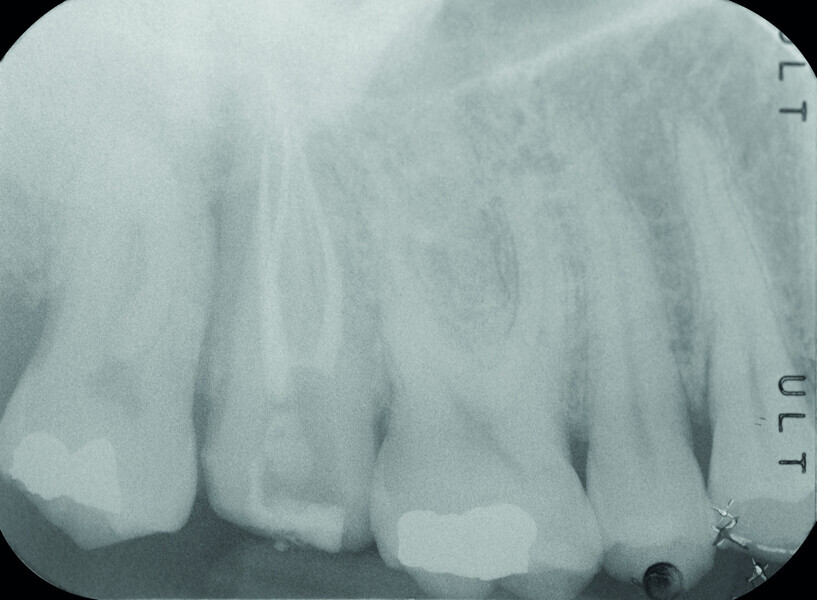

Fig. 16a: Pre-op periapical radiograph.